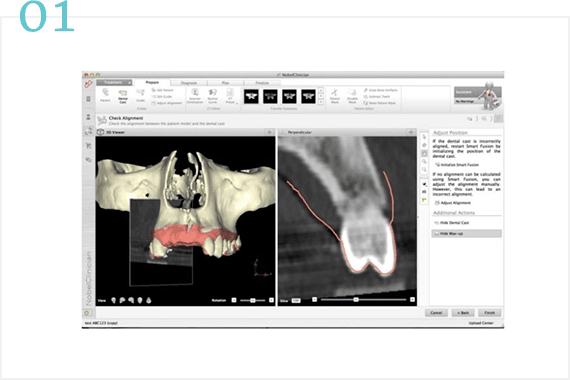

CASE 01

治療内容

ここにテキストが入ります

ここにテキストが入ります。ここにテキストが入ります。ここにテキストが入ります。ここにテキストが入ります。ここにテキストが入ります。ここにテキストが入ります。ここにテキストが入ります。ここにテキストが入ります。ここにテキストが入ります。ここにテキストが入ります。